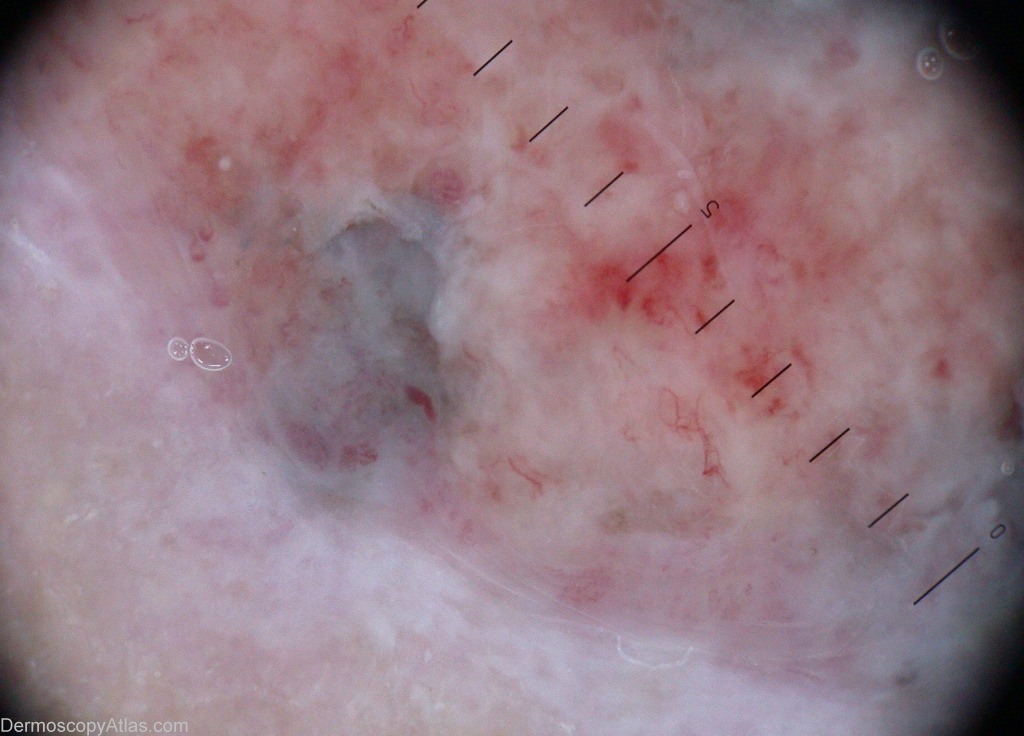

Image Number #2390 (Pigmented basal cell carcinoma)

Site: Leg

Diagnosis: Pigmented basal cell carcinoma

Description: Ulceration over the ankle, with a dark blue rim.

History: This lady came for a dark blue ulcerated lesion of a leg. Biopsy showed a pigmented basal-cell carcinoma. It is a twin case to case 189.